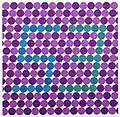

- De Standard Pseudoisochromatic Plates (SPP)

- Hiermee wordt kleurenblindheid nagegaan aan de hand van een vierkant vlak met gekleurde bolletjes. De patiënt moet zeggen welke cijfers er in het bolletjespatroon verborgen zitten. Hiermee worden alleen rood/groen-stoornissen (protan/deutan) getest.

SPP Test: zoek het getal dat tussen de gekleurde stippen zit. - De The City University (TCU)